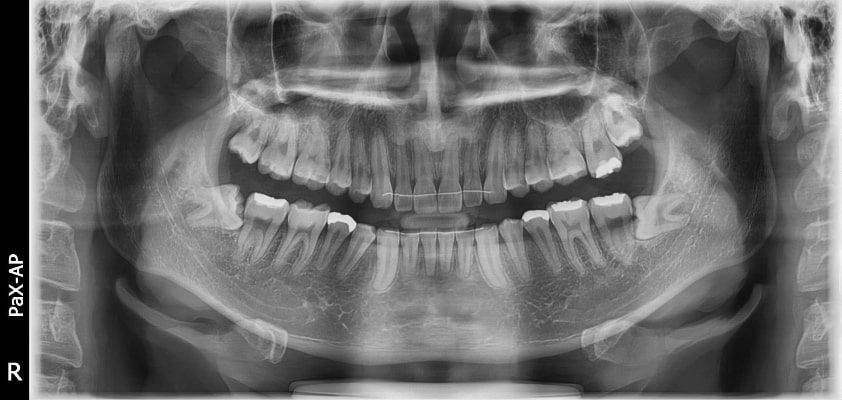

El innovador FOV proporciona un volumen en forma de arco que muestra una vista más amplia de la dentición en comparación con otros dispositivos del mismo FOV.

Normalmente, una imagen de 10x8.5 muestra el diente No.8. Sin embargo, cuando los terceros molares están tumbados sobre su lado hay una gran posibilidad de que el diente se corte de la imagen.

El “volumen en forma de arco” elimina esta posibilidad y muestra el área de dentición oculto.